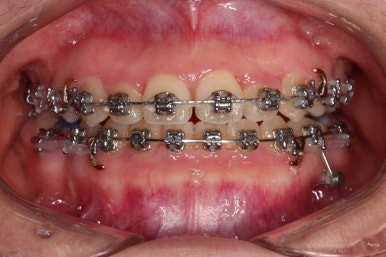

우선 장치를 저희 키다리아저씨치과에서 사용하는 장치로 바꿔 부착을 했어요.

세라믹에서 메탈로 안좋아진 것 아닌가요?

왼쪽이 처음 내원하셨을 당시의 입안 모습이고요. 오른쪽이 장치를 바꿔 부착한 이 후의 모습이에요.

세라믹에서 메탈로 다운그레이드 된 것처럼 보이죠?

사실은 훨씬 좋아진 장치랍니다.

유심히 보시면 왼쪽은 철사를 장치와 연결시키기 위해서 노란색 고무줄로 일일이 묶어줘야 하는 타입인데 비해, 오른쪽은 철사를 묶는 고무줄이 안보이죠?

바로 "자가결찰장치"라고 해서 브라켓에 일일이 뚜껑이 달려 있어서 철사를 장치 스스로가 직접 잡아주는 타입이에요.

그래서 메탈이라고 다 예전장치가 아니라는거죠.

메탈이라고 모두 예전 장치가 아니고 세라믹이라고 모두 최신 장치가 아닙니다.

자가결찰이 예전 장치에 비해 장점이 훨씬 많아서 아무리 세라믹이라고 한들 자가결찰 메탈이 훨씬 좋은 장치에요.